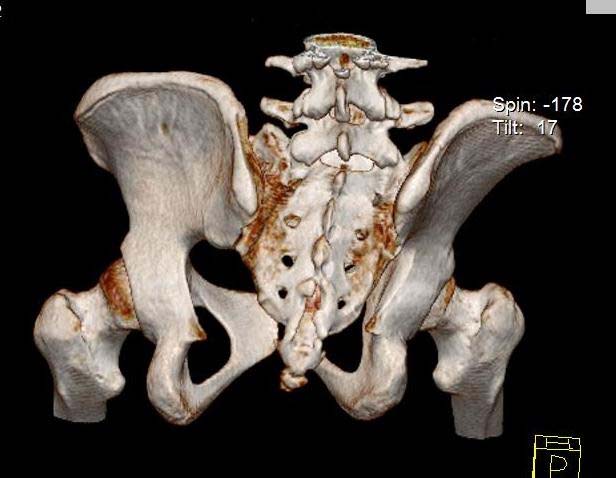

Больная 15 лет. Жалобы: на укорочение правой нижней конечности, хромоту.Анамнез: Со слов болеет с детства, травму отрицает. Ранее за медицинской помощью не обращалась. Последние 2 года отмечает резкое укорочение конечности. Локально: При осмотре отмечается умеренное искривление позвоночника во фронтальной плоскости, умеренная асимметрия лопаток и надплечий. Скошенность таза. Отмечается укорочение правой нижней конечности на 3 см. Движения в тазобедренном и коленном суставах в полном объеме. Нейрососудистых нарушений в периферических отделах нет.

Уважаемый Талгат. Просьба ответить на следующие вопросы: Укорочение у больной анатомическое или функциональное?

Как рентгенологи оценивают состояние крестцово-подвздошных сочленений, не создается ли впечатление о замыкании этого сочленения справа в предшествующие годы, а если это ощущение есть, то что привело к анкилозу этого сочленения. Нет ли по задней поверхности таза в указанной зоне рубца от имевшего место ранее свища?

Наверно целесообразно добавить,что болевого синдрома нет,движения в суставе в полном объёме.Я бы уточнил,что жалобы скорее косметического характера(асимметрия при ходьбе и западение вертельной области справа. Укорочение фигурировало как единственный диагноз в направлении на лечение к нам.Компенсация "укорочения" увеличением высоты каблука обуви не устраняет асимметрию таза и в статике и мало улучшает походку.Вопрос-стоит ли в конкретном случае идти на тройную остеотомию таза и латерализацию вертлужной впадины? Мне представляется,что не стоит.